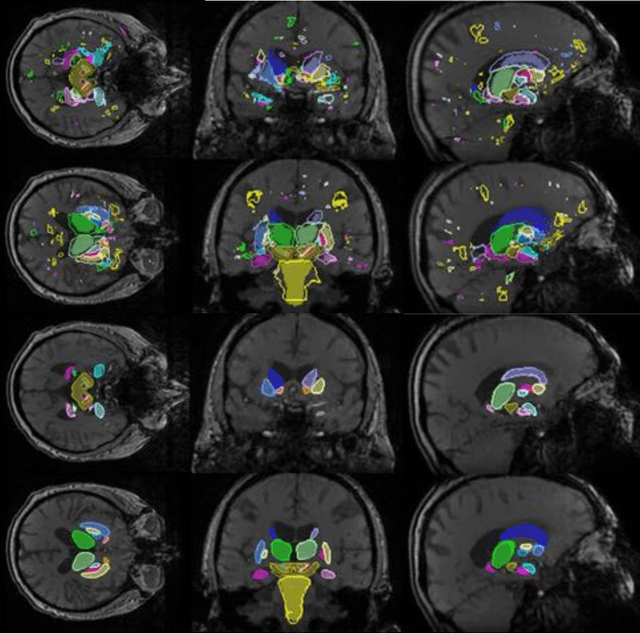

Abstract:In this work we propose a novel approach to perform segmentation by leveraging the abstraction capabilities of convolutional neural networks (CNNs). Our method is based on Hough voting, a strategy that allows for fully automatic localisation and segmentation of the anatomies of interest. This approach does not only use the CNN classification outcomes, but it also implements voting by exploiting the features produced by the deepest portion of the network. We show that this learning-based segmentation method is robust, multi-region, flexible and can be easily adapted to different modalities. In the attempt to show the capabilities and the behaviour of CNNs when they are applied to medical image analysis, we perform a systematic study of the performances of six different network architectures, conceived according to state-of-the-art criteria, in various situations. We evaluate the impact of both different amount of training data and different data dimensionality (2D, 2.5D and 3D) on the final results. We show results on both MRI and transcranial US volumes depicting respectively 26 regions of the basal ganglia and the midbrain.